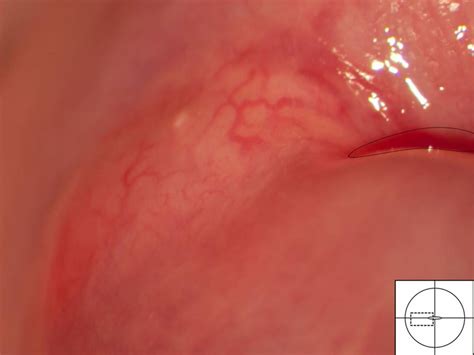

The most common type of cyst on cervix is known as a Nabothian cyst. These are small, benign lumps that form on the surface of the cervix. They occur when the glands that produce cervical mucus become obstructed by skin cells or inflammation, causing the mucus to build up and form a small, fluid-filled bump.

The cervix is covered in different types of cells. In the area known as the transformation zone, squamous cells (skin-like cells) can grow over the openings of the mucus-producing columnar glands. When this happens, the gland continues to secrete mucus, but because the exit is blocked, it gets trapped, creating a smooth, white or yellow bump that can feel firm to the touch.

Because they are rarely symptomatic, most cysts are detected incidentally. Your gynecologist will typically identify a cyst on cervix during a standard pelvic exam. The doctor can usually recognize the smooth, firm, rounded appearance of a Nabothian cyst by sight alone.

• Colposcopy: This involves using a specialized magnifying instrument to look closely at the cervix, allowing the doctor to get a better view of the tissue.